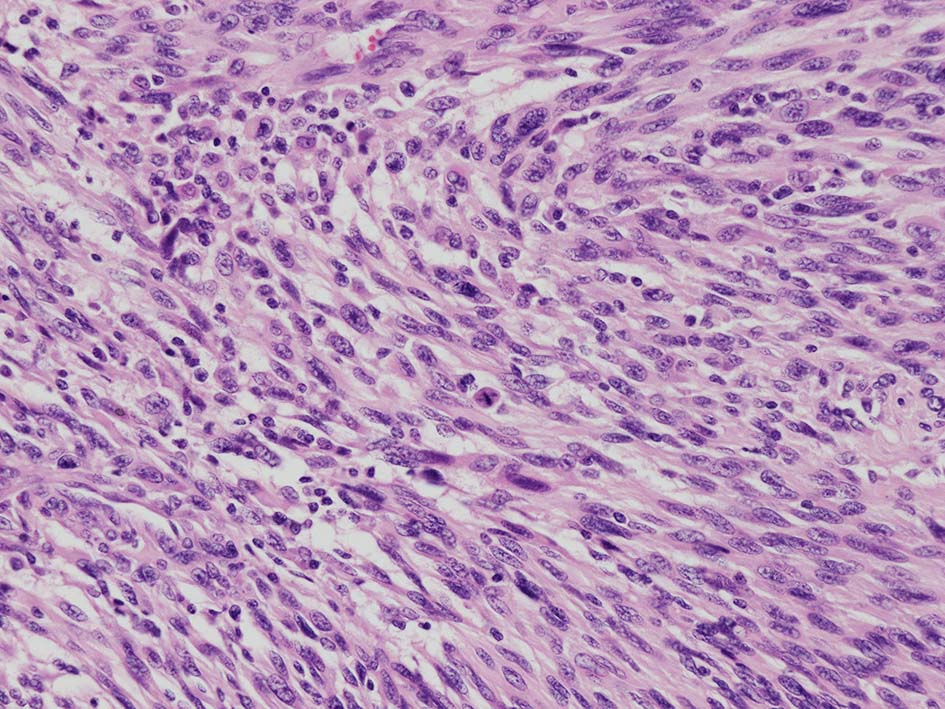

紡錘形異型メラノサイトが著明な間質反応(desmoplasia)を伴い増殖する特殊な色素性病変。*1. desmoplastic neurotropic melanomaは, desmoplastic melanomaのうち神経向性(neurotropism:神経周囲侵襲像)がめだつものでReedら*2が最初に報告した。

いずれも腫瘍細胞の異型性が乏しく, 背景の間質反応がめだつこと, メラニンの存在が目立たないことが特徴である。

“このため両者を臨床的にも病理学的にも色素性病変と診断することが困難”であり, 初回生検時には瘢痕病変や皮膚線維腫などと誤認されることが多い。